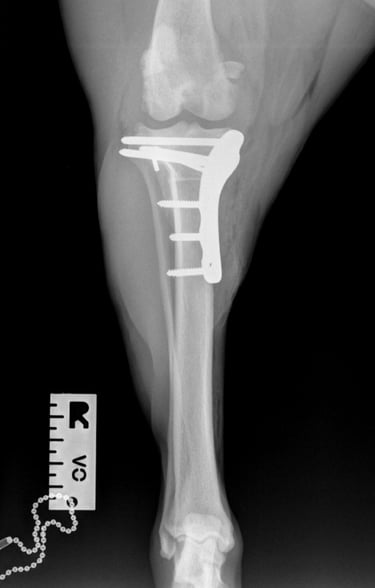

At the first postoperative recheck (day 3), Luna was nearly fully weight-bearing with only mild lameness. The surgical site showed excellent healing and 6 weeks post-op xrays (Figs. 7 and 8) show good ossification of osteotomy line and good position of implants.

Fig. 7

Fig. 8